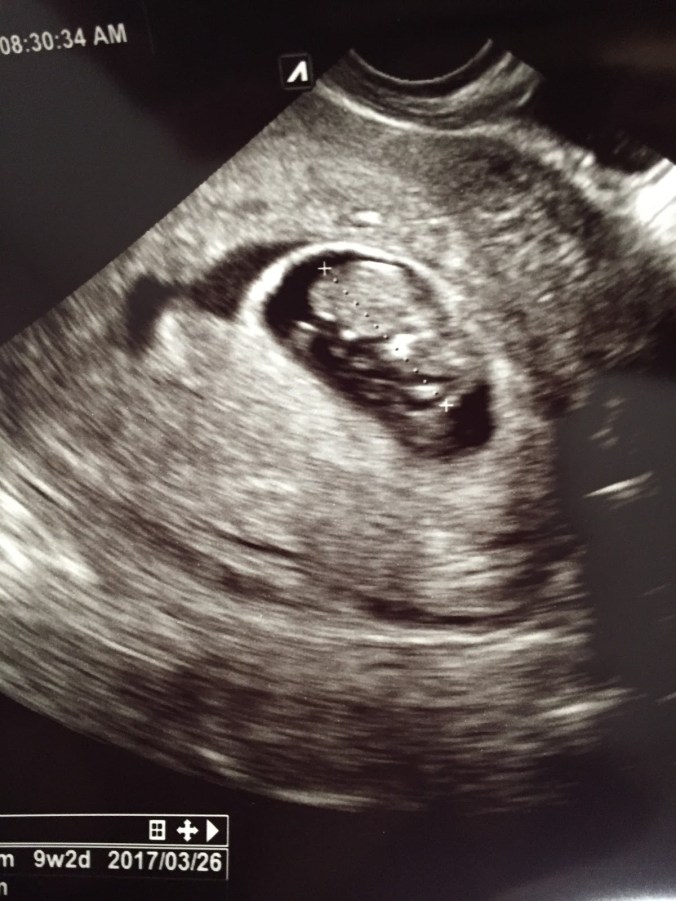

Tisdag 23/8 (9+2)

Idag var det äntligen dags för VUL nr 2, och visst fick jag se en sprattlande liten krabat med ett fint tickande hjärta! Läkaren mätte det till 9+2, samma som enligt min beräkning, så det kändes som att allt är bra och stämmer. Idag kommer jag berätta för närmsta kompisarna!